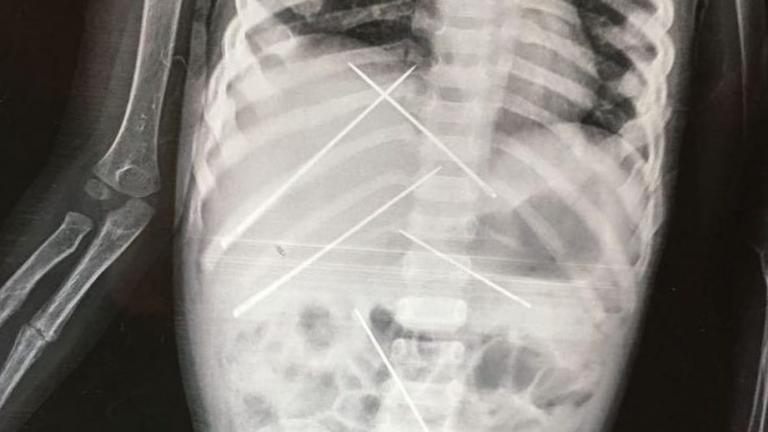

ΔΙΕΘΝΗ 20/07/2017 - 12:13 ΣΟΚ - Γεμάτο βελόνες το κορμί τρίχρονου παιδιού από μαύρη μαγεία Γέμισαν το κορμάκι τρίχρονου παδιού με βελόνες κάνοντας τελετές μάυρης μαγείας - Εικόνες που σοκάρουν